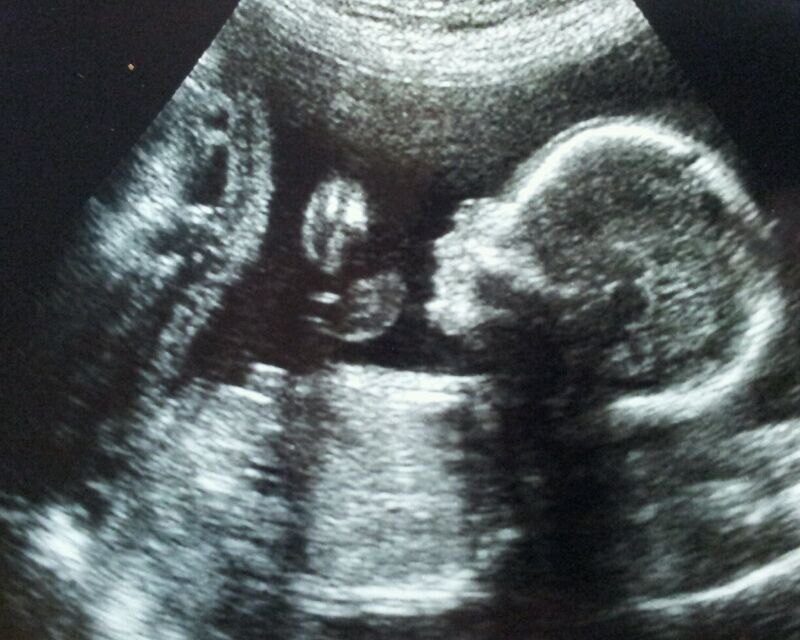

Медики подсчитали, сколько абортов делается в России: цифра невероятная. Врачи пришли в ужас. Вот где настоящая война! Рожать или не рожать: как мы убиваем своих детей, количественно и качественно. Из года в год статистика не радует. Самых свежих данных нет, потому что частные клиники не делятся своими данными. А они ужасают. Смотрите цифры за 2022...